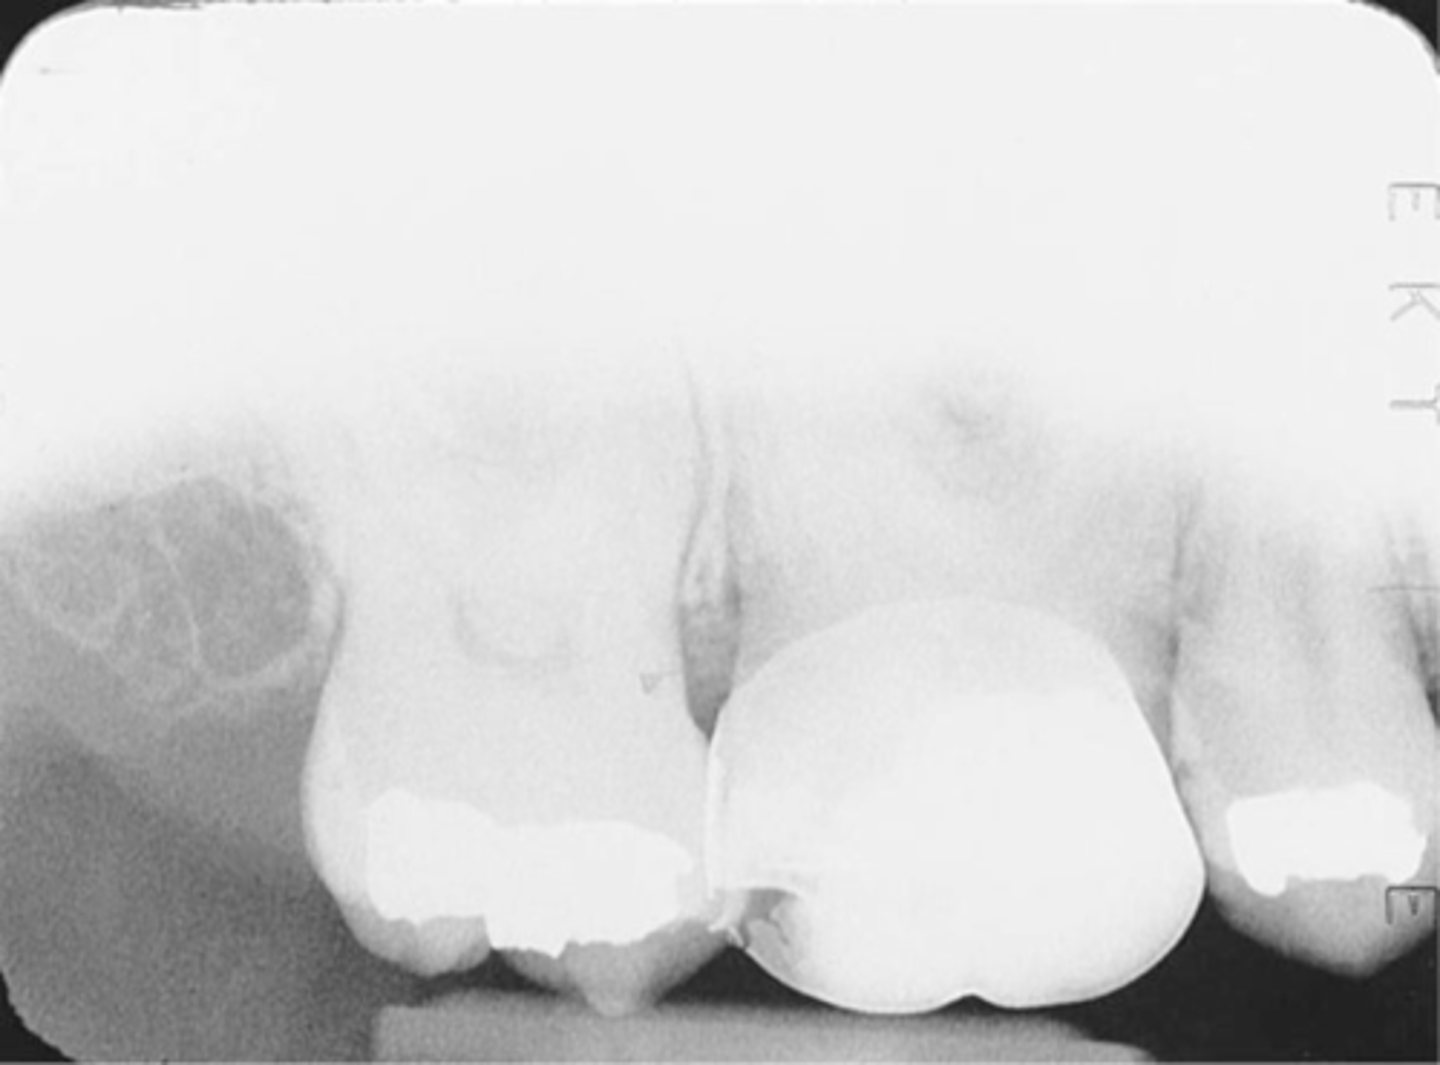

dropped receptor corner

edge of receptor not placed parallel to occlusal plane

bite firmly on bite block